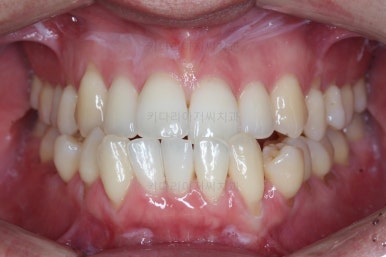

부산비수술교정 키다리아저씨치과에서 시행한 이번 치료의 결과입니다.

옆모습이 주걱턱 느낌이 많이 없어졌고 볼록하던 아랫입술도 뒤로 들어갔어요. 앞니가 거꾸로 물리지 않게 되어 웃거나 말하는 모습도 자연스러워졌어요.

아랫니 갯수가 모자라고 중앙이 맞지 않았고 짝이 안맞는 상황이었으나 비교적 잘 마무리를 했어요.

거꾸로 물리는 상황이 개선되었기 때문에 앞니나 어금니의 교합은 이전과 비교할 수 없을만큼 좋아졌지요.

전후 모습을 비교해 보겠습니다.

왼쪽이 치료 전, 오른쪽이 치료 후 모습입니다.